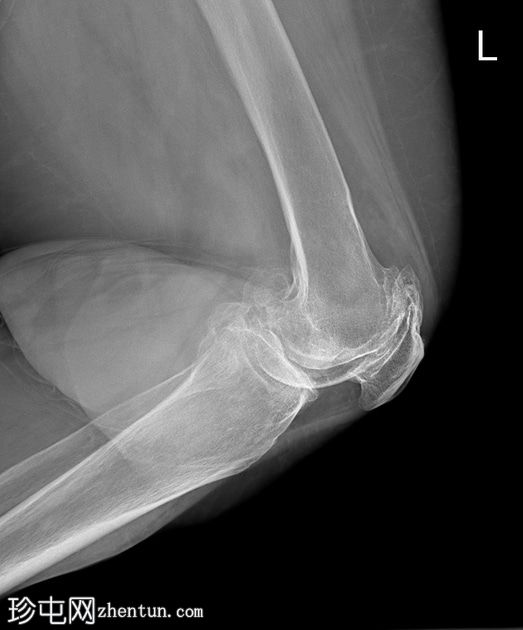

双膝X线片

X线片

正位片

侧位片

双侧胫股关节间隙明显变窄,伴软骨下硬化。

双侧髌股关节间隙变窄。双侧股骨和胫骨关节周围骨赘及髌骨骨赘。

右侧股骨远端软组织内可见多发致密钙化分叶状病变。未见骨折、骨膜反应或骨损伤。无内翻或外翻畸形。